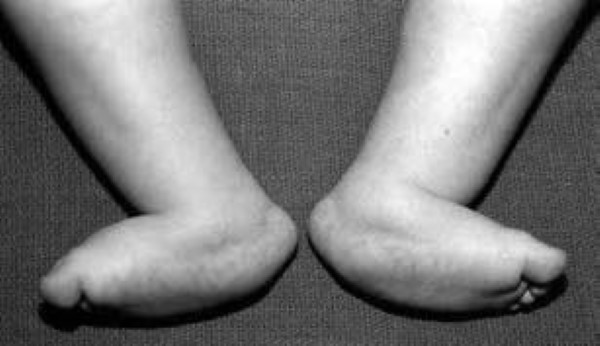

vertical talus in bone feet

This 9-month-old infant has vertical talus in both feet.

Reproduced from Kasser JR, ed: Orthopaedic Knowledge Update, ed 5. Rosemont, IL, American Academy of Orthopaedic Surgeons, 1996, p 507.